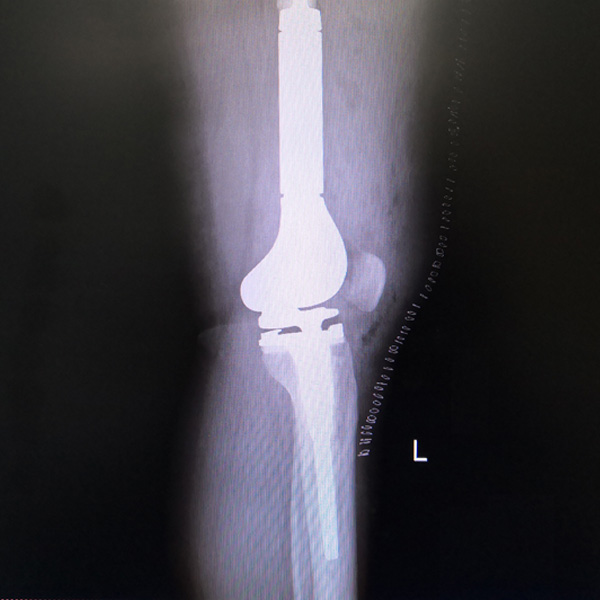

骨肉瘤手術(shù)

患者張某,女,14歲,診斷為“左股骨遠端骨肉瘤”,當(dāng)?shù)蒯t(yī)院因為醫(yī)療技術(shù)和能力的限制,只能考慮截肢手術(shù)。患者家屬通過平臺推薦,指定到哈......